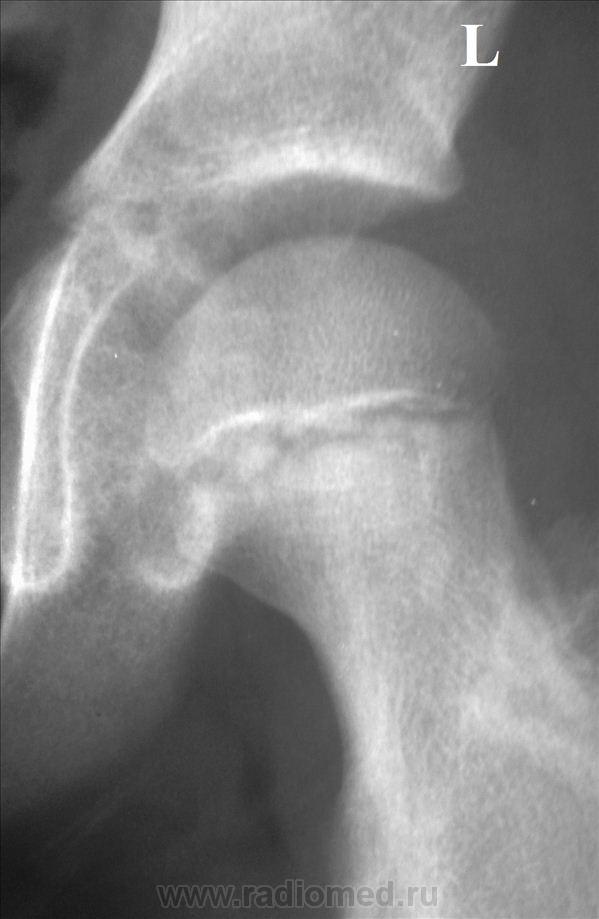

Случай по дежурству. Мальчик 8 лет. стал испытывать боль в правой нижней конечности около недели назад, несмотря на это продолжал активно заниматься футболом. Вчера боль в т\бедренном суставе резко усилились, появилось вынужденное положение, незначительная ротация бедра кнутри, и сгибание коленного сустава 175 гр, осевая нагрузка на нижнюю конечность не возможна из-за выраженного болевого синдрома, температура 37,4, в ОАК лейкоцитоз 13.4, палочки 9, СОЭ 28 мм\час. На рентгенограмме т\бедренных суставов мне не понравился медиальный участок суставной поверхности головки правого бедра. Можно ли данный случай считать начальным проявлением болезни Пертеса?

Александр Викторович, здравствуйте.Спасибо, что не выполнили обещание. Первое, на что обратила внимание-укорочение шейки левой бедренной кости,увеличение ШДУ( укладка, дисплазия?). Первая стадия болезни Пертеса рентгеннегативна.Цитирую И.А.Шехтера."Начальным рентгенологическим признаком является ф дальнейшем наступающее расширение рентгеновской суставной щели.Вторая стадия характеризуется наличием резко повышенной интенсивности тени эпифизарной головки, которая уменьшена в размерах, несколько деформирована и сплющена вследствие импрессионного перелома.Одновременно уже хорошо выявляется значительное расширение рентгеновской суставной щели.Почти как правило ,обнаруживается небольшой подвывих бедра, который остается на протяжении всего заболевания".Динамика нужна.Если есть клиника ( а я не сомневаюсь, что Вы замечательный клиницист), то , конечно,Вы все правильно делаете.Жду мнение уважаемых коллег.

Наверное, начальные проявления все-таки есть в виде небольшой деформации головки .Интересно, а кто-нибудь ставил первую-вторую стадии болезни Пертеса?Я чаще всего наблюдала уже исход.Как-то даже пациентка была из Белгорода, где ей упорно ставили ДОА.Приехала к родственнице-нашей коллеге.Мы ей Пертеса поставили, областные травматологи подтвердили, прооперировали.Женщина счастлива и довольна.Столько лет мучилась, а на Сахалине ей помогли.Вот хвастаюсь.

Думаю, что о болезни Пертеса говорить рано, явной деструкции и подвывихов нет, отмирать должны участки головки, контактирующие именно с крышей вертлужной падины. А здесь якобы страдает медиальная поверхность. Но обратите внимание - при сравнении с контрлатеральной головкой на снимках видны не симметричные участки, а другие, что обусловлено несимметричностью бедер, углы ротации бедер при снимке - не равны. Еще - есть явная рабочая гипертрофия внутренних полуцилиндров бедер, а шеечно - диафизарный угол слева - увеличен. Слева - легкая неоднородность в структурах шейки бедра, но возможно это остеопороз...

Лаунштейна бы, для полного счастья... Ибо ЮЭГБ не дремлет. А на Пертеса вроде бы не похоже.

Особенно если обратить внимание на структуру наружно-нижнего края эпифиза бедра справа, неравномерность щели между эпифизом и метафизом справа, легкую неконгруентность справа...да и футбол из той же оперы....

Я бы предположила юношеский остеоэпифизиолиз головки бедра, достаточно убедительная картинка.

Ни за болезнь Пертеса, ни за эпифизеолиз данных не вижу, скорее всего, у ребенка артрит. Хорошо бы УЗИ сустава.